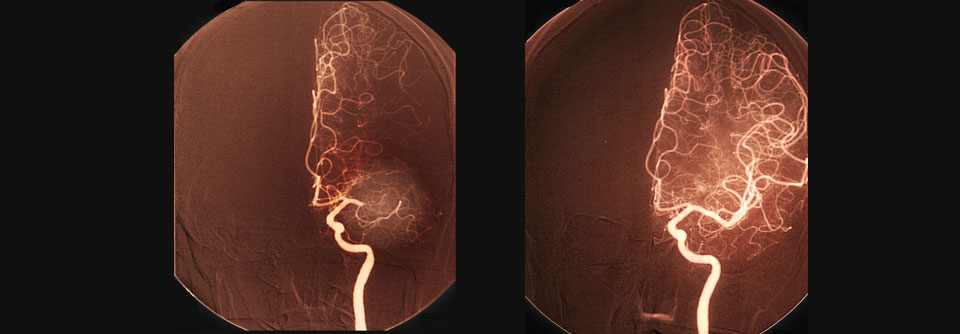

Wie schon bei früheren Interfaces dieser Art beruht die neue Technik darauf, dass zerebrale Signale in Text umgewandelt werden – mit einer Geschwindigkeit von fast 80 Wörtern pro Minute. Dazu wird ein papierdünnes Rechteck mit 253 Elektroden auf die Oberfläche des Gehirns gelegt, direkt über den Arealen, die für die Sprache relevant sind. Die Elektroden registrieren die Hirnsignale, die ohne den Schlaganfall an die Muskeln von Zunge, Kiefer, Larynx und Gesicht der Patientin geleitet würden.